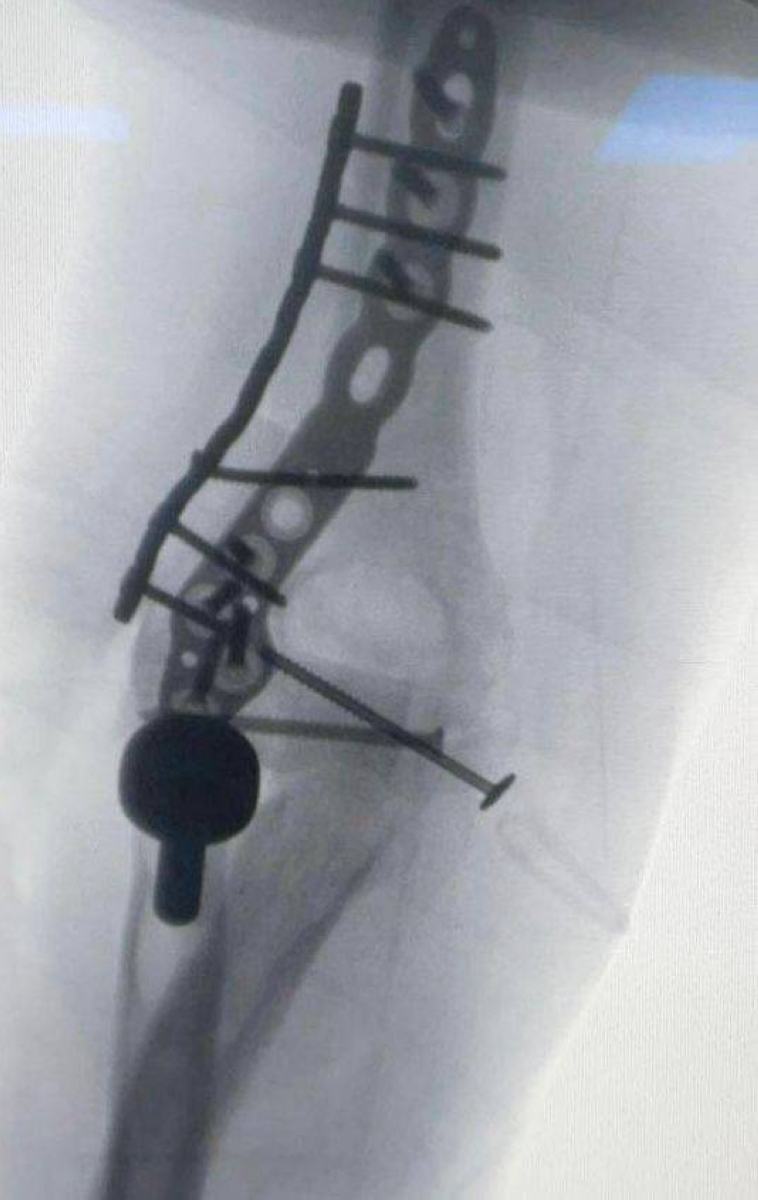

In a medical achievement that is the first of its kind in the Eastern Province, a medical team at King Fahd University Hospital in Khobar - part of the Academic Medical City at Imam Abdulrahman bin Faisal University - successfully performed a rare and complex surgical procedure involving the implantation of an elbow joint and the reconstruction of the surrounding ligaments for a young man after he suffered a serious injury resulting in a compound fracture, significant loss of the joint, and damage to the surrounding tissues.

The surgical team was led by Dr. Saad Al-Qahtani - Head of the Orthopedics Department and Consultant in Orthopedic Surgery and Upper Extremities - who explained that the team handled the case meticulously from the very beginning, starting with examining the patient in the clinic, conducting laboratory tests and X-rays, and collaborating with Dr. Mohammed Barjah from the Biomedical Engineering Department to utilize 3D printing technology to accurately determine the size of the missing part of the joint.

Dr. Al-Qahtani pointed out that such cases are often treated by installing a prosthetic joint; however, the young age of the patient led the team to make an exceptional decision to implant bone and a joint from a donor, along with reconstructing the surrounding ligaments, with the aim of preserving elbow function and providing the patient with the best possible outcome.